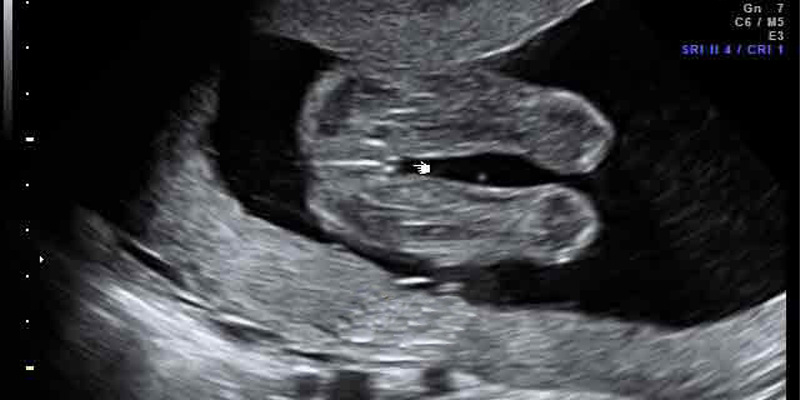

Критические точки, важные с точки зрения физиологии – 3 и 8 месяцев с момента зачатия: в эти сроки у ребёнка происходит мощная гормональная перестройка. Малейший стресс – мама испугалась, увидела некрасивую картину и т.д. – может привести к тому, что ребёнок поменяет пол физиологически. Это доказано медиками.

Часто бывает, что женщина делает УЗИ на 6-7 месяце и ей говорят: «Будет мальчик», – а рождается девочка или наоборот. Это нормально, поскольку человеку дано Богом столько сил, что он может перестроить всё что угодно, не говоря уже о собственном физическом теле.